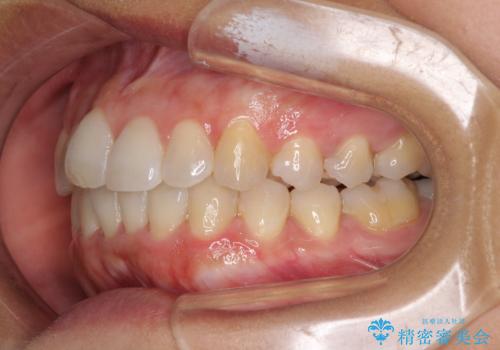

前歯のデコボコをインビザラインでスッキリと仕上げる

- 上下前歯のデコボコと奥歯の銀歯を気にして来院された患者様です。

口元をインビザラインにより歯列を整え、その後に失活している奥歯をオールセラミッククラウンにて補綴治療することとしました。

長時間のマウスピース装着に協力いただき、自然な口元に仕上げることができました。

気になっていた銀歯もオールセラミッククラウンで本物の歯のようになり、患者様には大変満足していただきました。